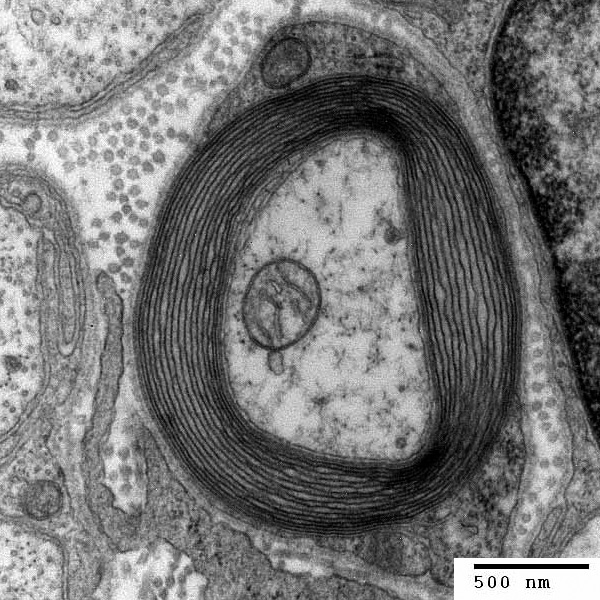

Diese Isolation namens Myelin besteht aus vielen Lagen von Zellmembranen. Im Querschnitt gleicht ein auf diese Weise isoliertes Axon den Jahrringen eines Baums. In regelmässigen Abständen sind diese Myelinscheiden eingeschnürt. Um schnell voranzukommen, springen Nervenimpulse von einer Einschnürung zur nächsten.

Verantwortlich für den Aufbau der Isolation von Axonen sind die sie umgebenden Schwann-Zellen. Sie verbrauchen in kürzester Zeit, meist in den Monaten nach der Geburt, grosse Mengen an verschiedenen Fettmolekülen (Lipide), um Axone mit Myelin zu ummanteln. Wie sie den grossen Lipidbedarf decken, war bislang unbekannt. Wissenschaftler waren sich uneins, ob Schwann-Zellen diese Moleküle aus der Nahrung beziehen oder ob sie diese selbst produzieren.